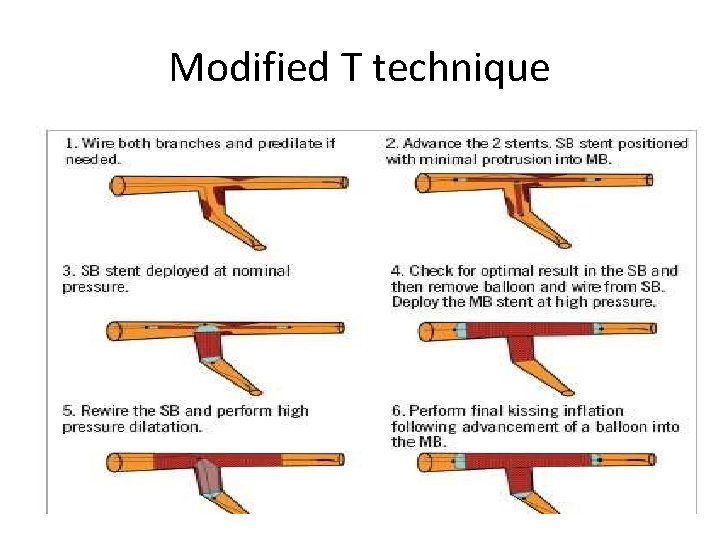

Stenting techniques 1)Provisional • Mainvessel stenting ± side branchangioplasty (Provisional) Tstenting, • TAP, • REVERSEINTERNAL CRUSH • REVERSECULOTTE. 2) elective • Culotte-stenting • Crush technique (reversecrush) T TECHNIQUE AND TAP • V STENTING • Y STENTING(SKS technique)

Modified T technique